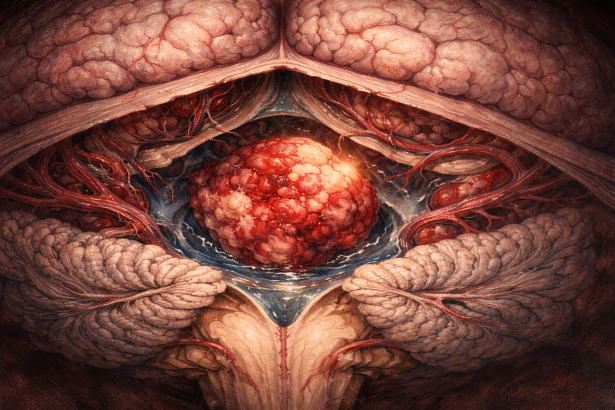

Definiție și originea tumorii

Ependimoamele sunt tumori gliale care iau naștere din celulele ependimare – celule care căptușesc ventriculii creierului și canalul central al măduvei spinării. Aceste celule au rolul de a contribui la circulația lichidului cefalorahidian (LCR), iar tumorile provenite din ele se dezvoltă în mod tipic în apropierea sistemului ventricular sau în măduva spinală. Ependimoamele pot apărea atât la copii, cât și la adulți, însă sunt mai frecvente la copii, mai ales în fosa posterioară.

2. Biopsie și analiză histopatologică:

Este esențială pentru stabilirea diagnosticului. Se observă celule ependimare, uneori cu rozetă perivasculară (tipică). Întrucât ependimoamele sunt tumori intraventriculare, celulele tumorale pot fi prezente și în LCR, unde se pot pune în evidență prin examen citologic.